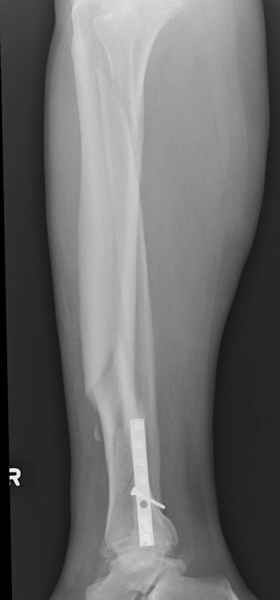

спрашивает что делать с больным который поступил недавно, фермер 55 лет падение при пьяной драке в баре, года два назад перенес операцию на лодыжке, на снимках и КТ перелом без вовлечения сустава,

Повреждение такой локализации, на которой применимы и аппарат (классический Илизарова или гибридный), пластина, особенно Locked Plate, и гвоздь с блокированием. В нашей клинике был бы выполнен закрытый интрамедуллярный остеосинтез. Желательно использовать гвоздь с возможностью провести более чем 2 обычных фронтальных винта в дистальном отломке.

Здесь мы использовали новый Synthes Nail с дополнительными дырками, в проксимальной части 4: по две косых и поперечные (один стандартный а другой динамический), в дистальной части две поперечные, прямая и косая. Вес больного более 120 кг, нагрузку начнем через месяц.

При такий спирали задний край tibia может быть сломан - нет ли этого в данном случае? На всякий случай можно было ввести 1-2 винта 4,5 мм спереди назад мимо гвоздя. Хотя самый дистальный блокирующий винт, возможно, зацепил этот отломок. А какой тут диаметр гвоздя и locking винтов?